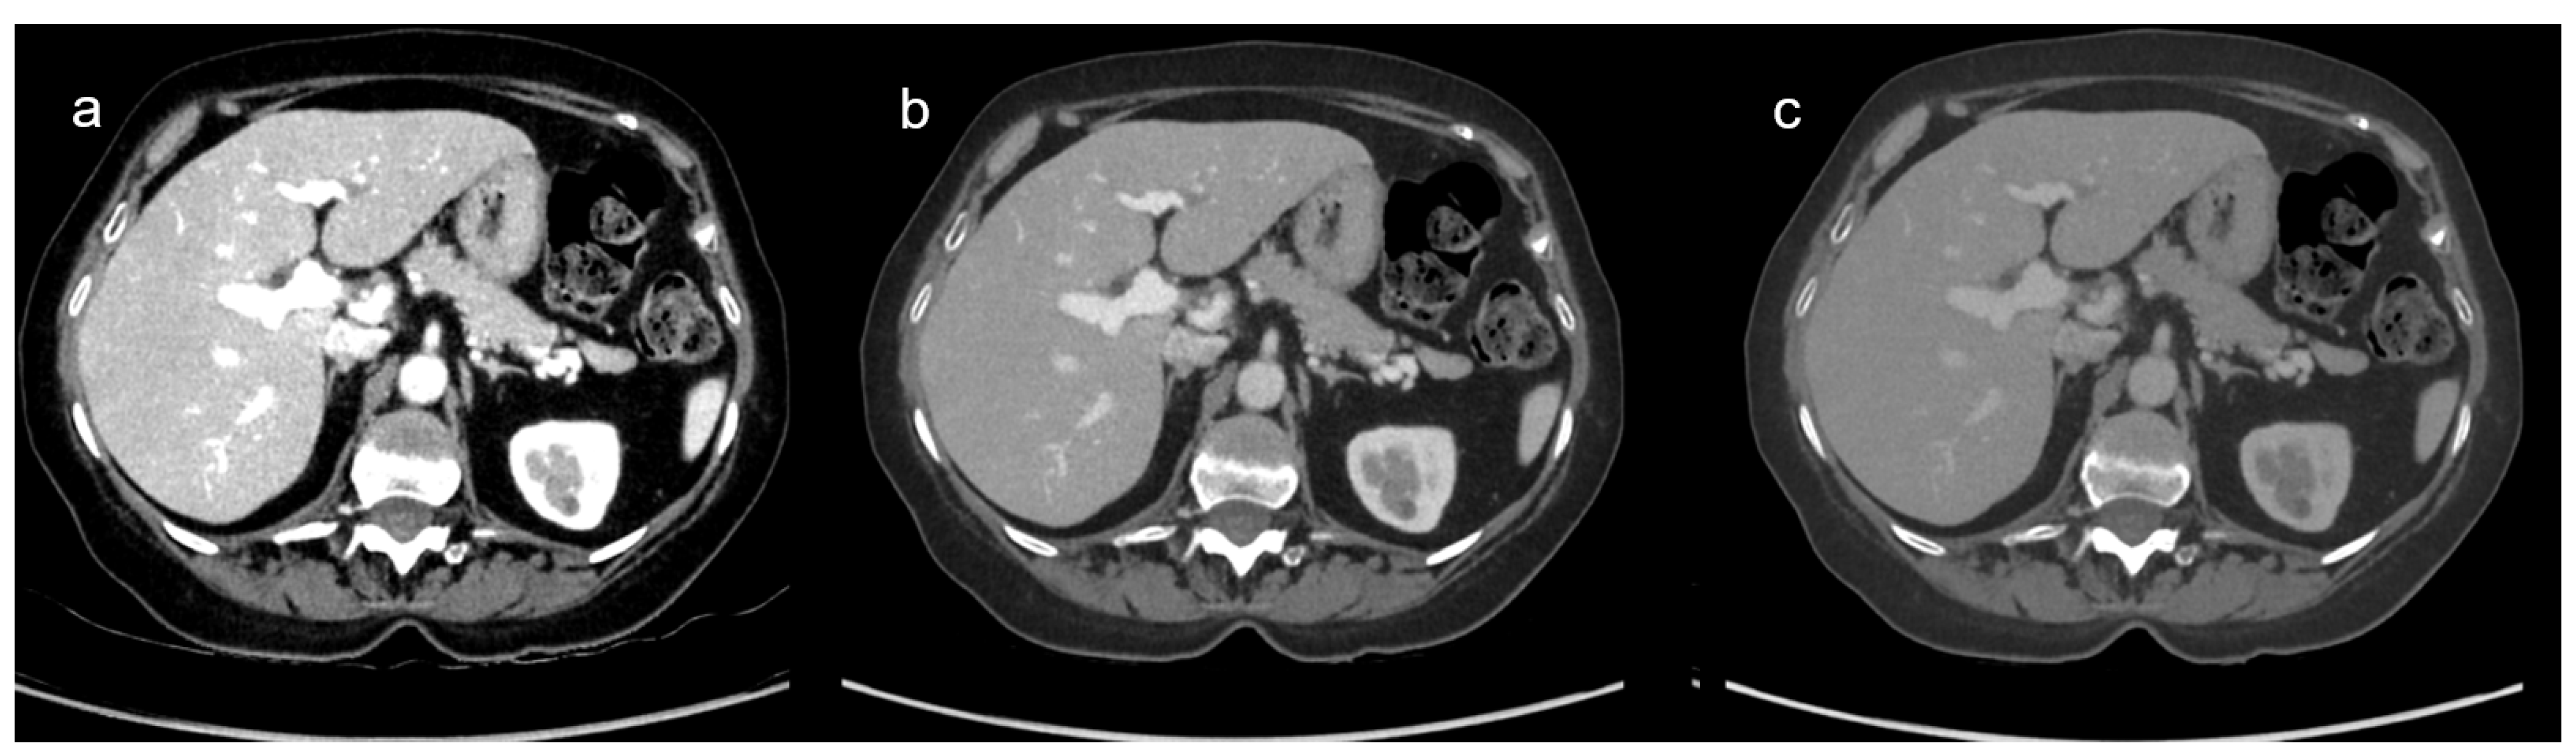

3.2.1. VMI Comparison: Qualitative Results

3.2.2. VMI Comparison: Quantitative Analysis Results

3.3. Comparison of DECT and SECT Results

3.3.1. DECT and SECT Comparison: Qualitative Results

3.3.2. DECT and SECT Comparison: Quantitative Analysis Results